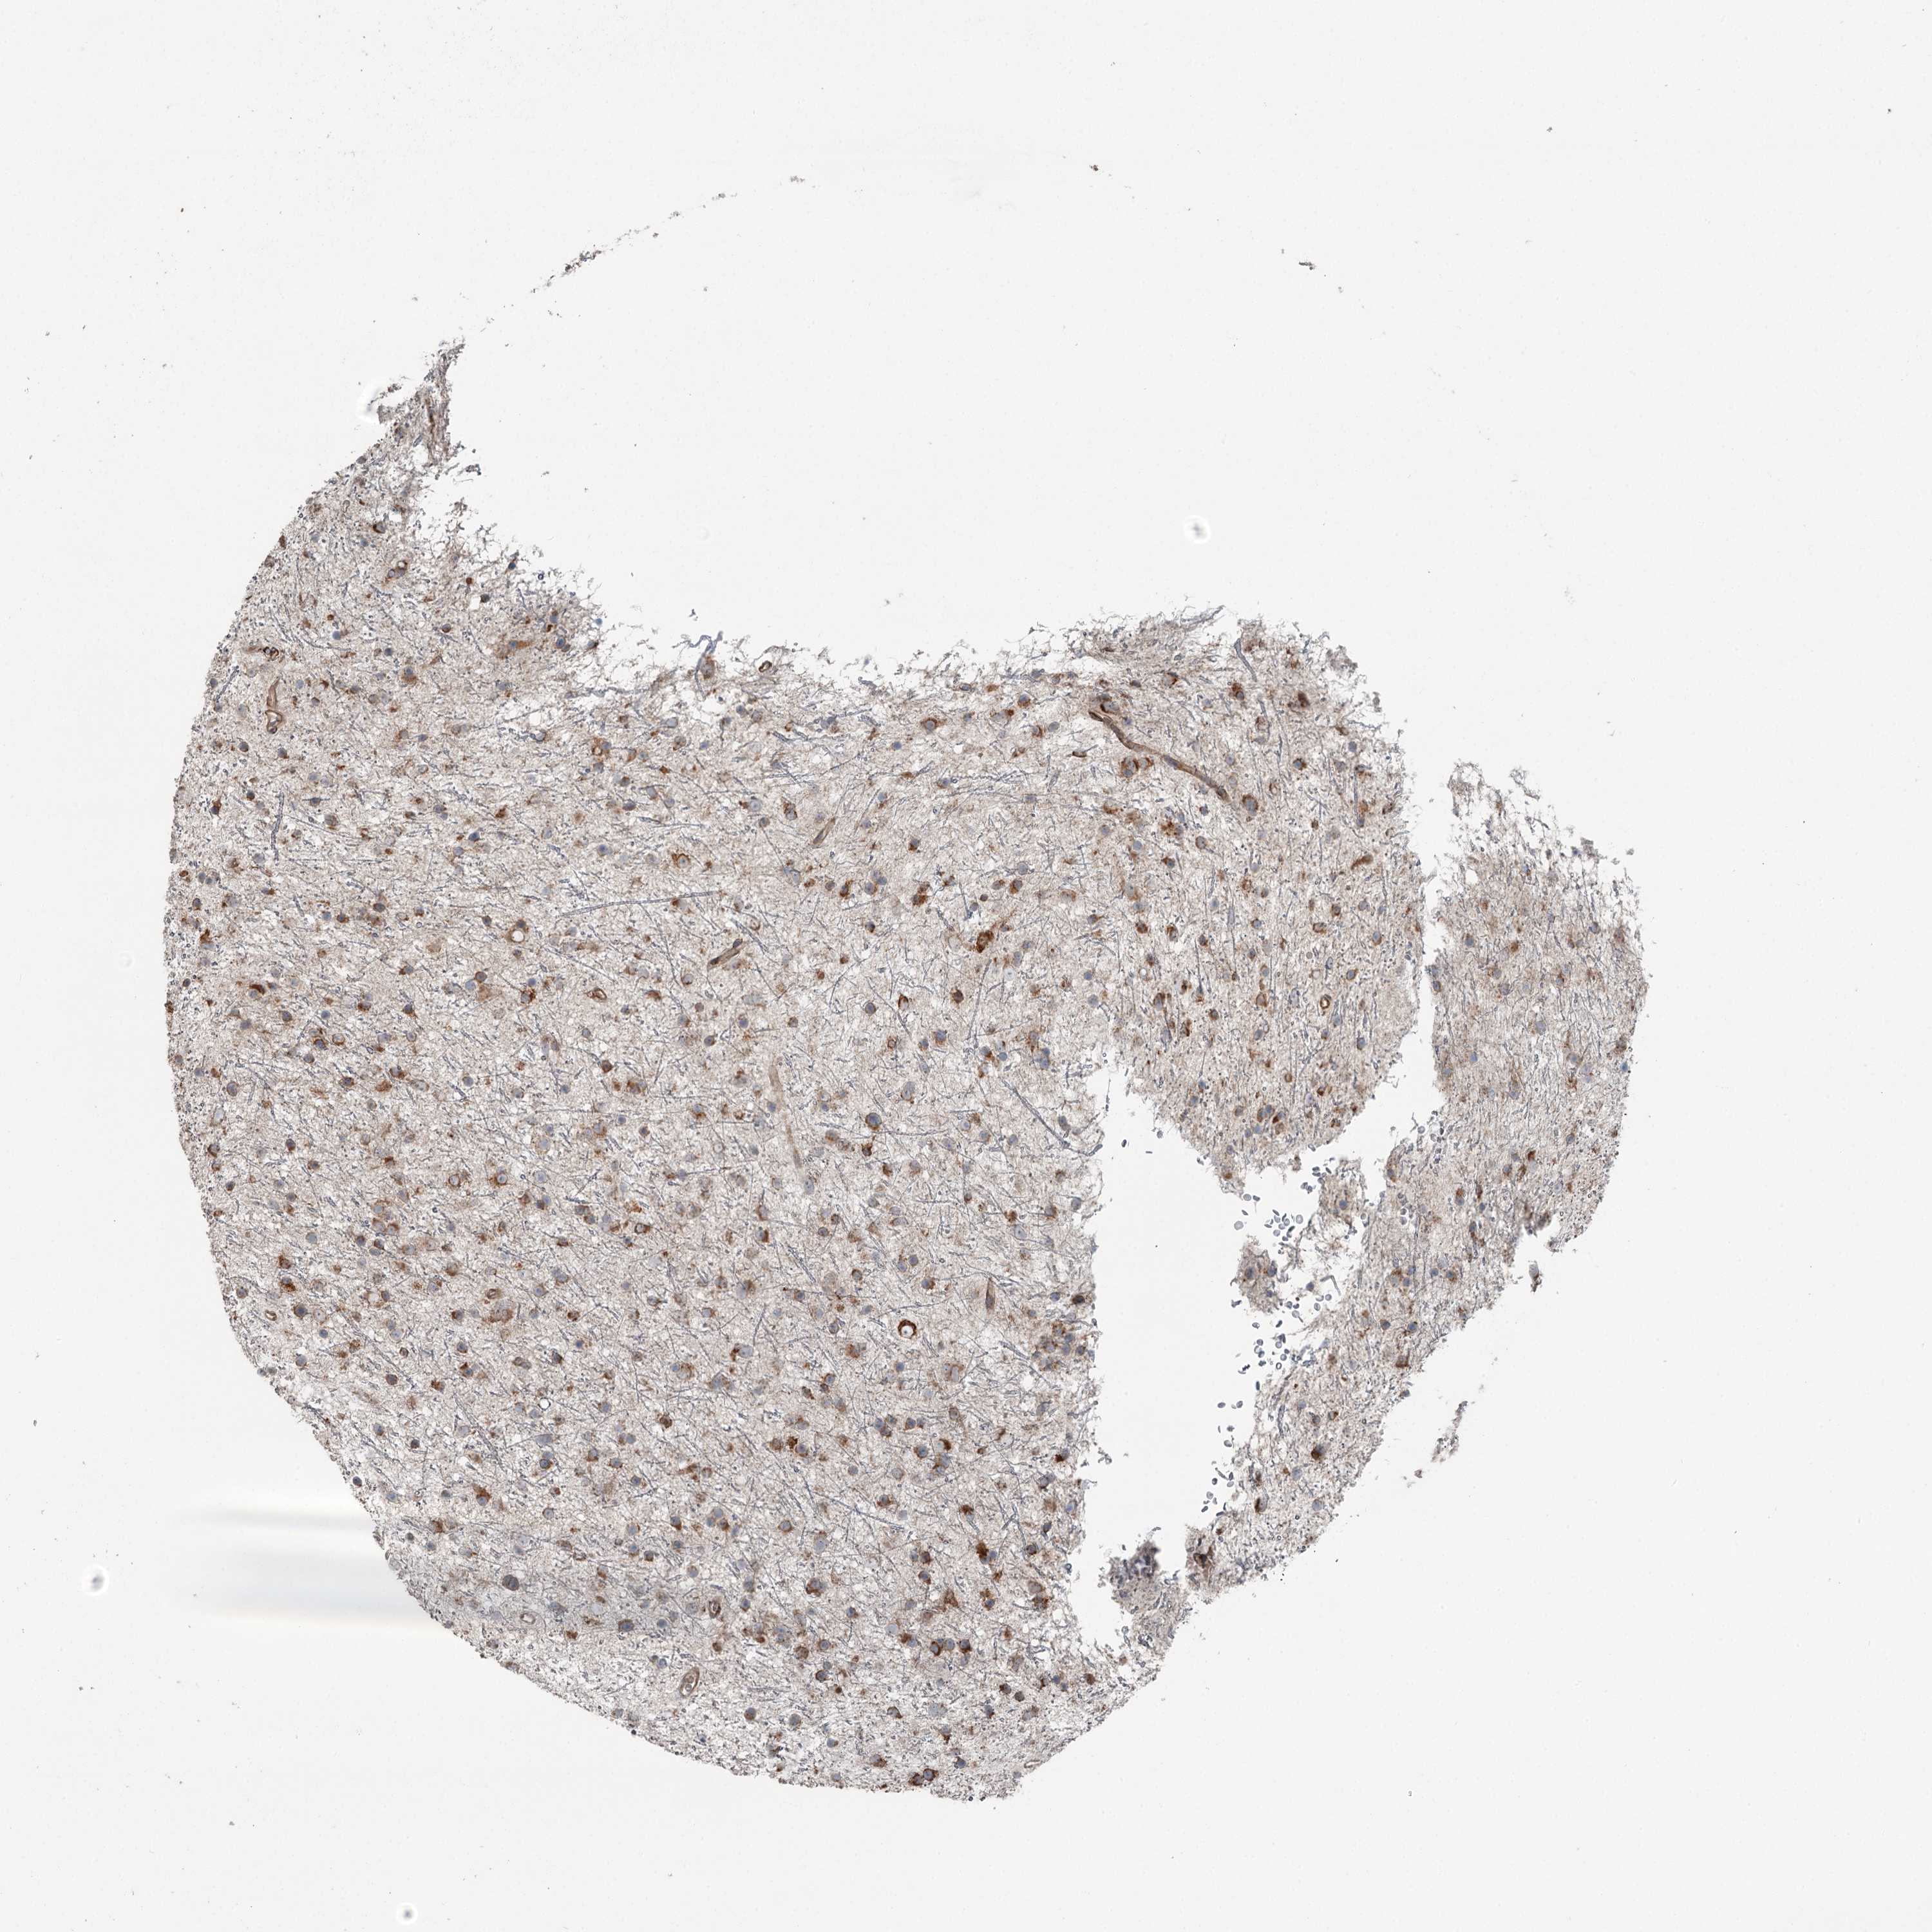

GLIOMA - Protein expressioni

A mouse-over function shows sample information and annotation data. Click on an image to view it in a full screen mode. Samples can be filtered based on level of antibody staining by selecting one or several of the following categories: high, medium, low and not detected. The assay and annotation is described here.

Note that samples used for immunohistochemistry by the Human Protein Atlas do not correspond to samples in the TCGA dataset.

Antibody stainingi

Antibody staining in the annotated cell types in the current human tissue is reported as not detected, low, medium, or high, based on conventional immunohistochemistry profiling in selected tissues. This score is based on the combination of the staining intensity and fraction of stained cells.

Each image is clickable and will lead to virtual microscopy that enables deeper exploration of all samples and also displays staining intensity scores, fraction scores and subcellular localization as well as patient and tissue information for each sample.

Antibody HPA038163

Antibody HPA038164

Glioma, malignant, High grade

Glioma, malignant, Low grade

Glioblastoma, NOS